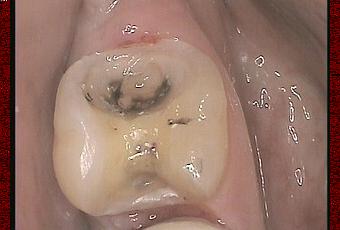

L'onlay permet parfois d'éviter la couronne (et la dévitalisation qui l'accompagne généralement) sur des dents fortement délabrées ou en remplacement d'anciens amalgames. Après dépose d'un amalgame infiltré, sur un jeune homme, nous sommes dans la situation de la première photo.

La substance manquante de la 47 est importante et il y a une proximité pulpaire après éviction de la dentine infectée...

Photo pré-op amalgame déposé